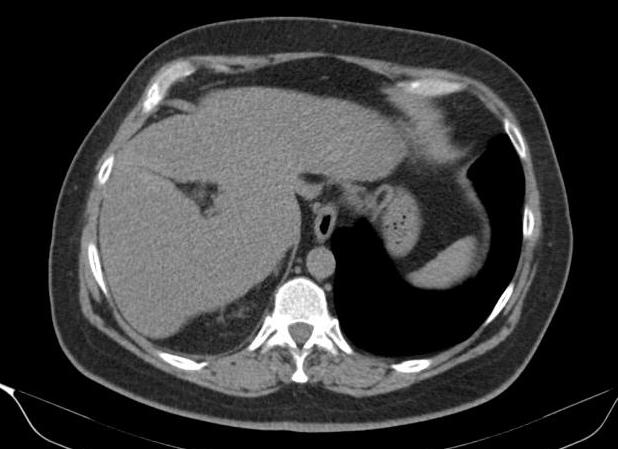

Túi thừa dạ dày - Ảnh 3

Túi thừa dạ dày

» Thông tin: Nữ giới – 54 tuổi.

» Lâm sàng: Kiểm tra sức khỏe.